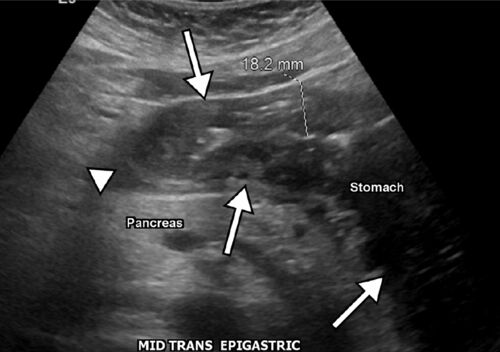

病歴/身体所見 ・60歳男性 ・刺身を食べてから8時間後に重度の上腹部痛を発症してER受診 ・バイタルサインには異常なし 検査 ・血液検査でも特記すべき異常は認めなかった ・腹部超音波では、胃壁の腫脹と胃内に高エコーのlineを認めた ※本case reportには超…